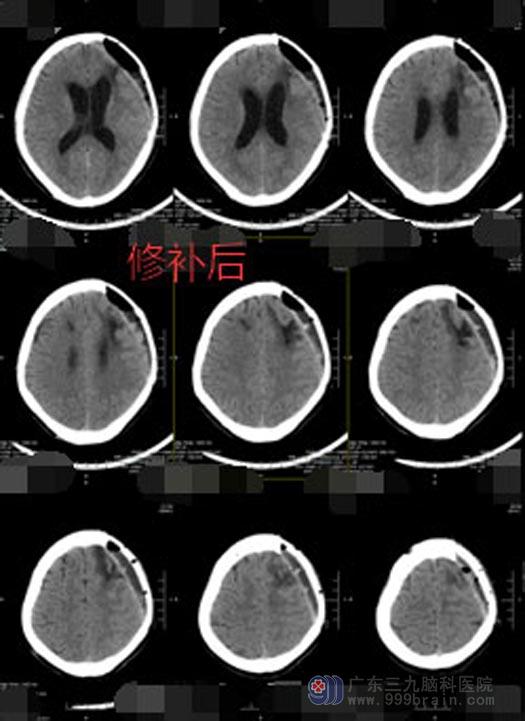

看到这个不一样的妻子,陈大哥特别心疼和感动,虽然右侧肢体偏瘫,但对他们一家来说这已经是很好的结果了。目前陈大哥病情好转,神志清楚,已经完成了颅骨修补。

这个家已经负债累累,但是妻子说,要选用最好的材料给丈夫补颅骨,“他能好起来比什么都重要,钱以后会慢慢挣回来的”。

▲颅骨修补后CT